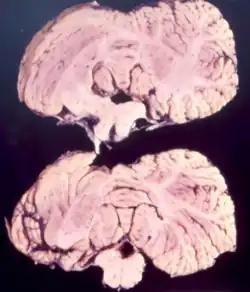

Cerebellum of a person infected with kuru.

Studies from kuru infected individuals have revealed information explaining the effects that the disease can have on the brain. In the early stages of the disease, infected individuals may experience withdrawal, incoordination, tremors, and curling of the toes and feet.[17] To understand these difficulties in balance and coordination, studies were conducted to analyze the brain of kuru infected individuals. These studies by Klatzo et al., found that neurons in a kuru infected brain were abnormally small and lighter in color compared to their healthy counterparts.[17] Affected neurons appear "moth-eaten" due to their characteristic deformations. [17] These abnormalities in the neurons of the brain infected by kuru were similar to those with Creutzfeldt-Jakob disease (CJD).[17]